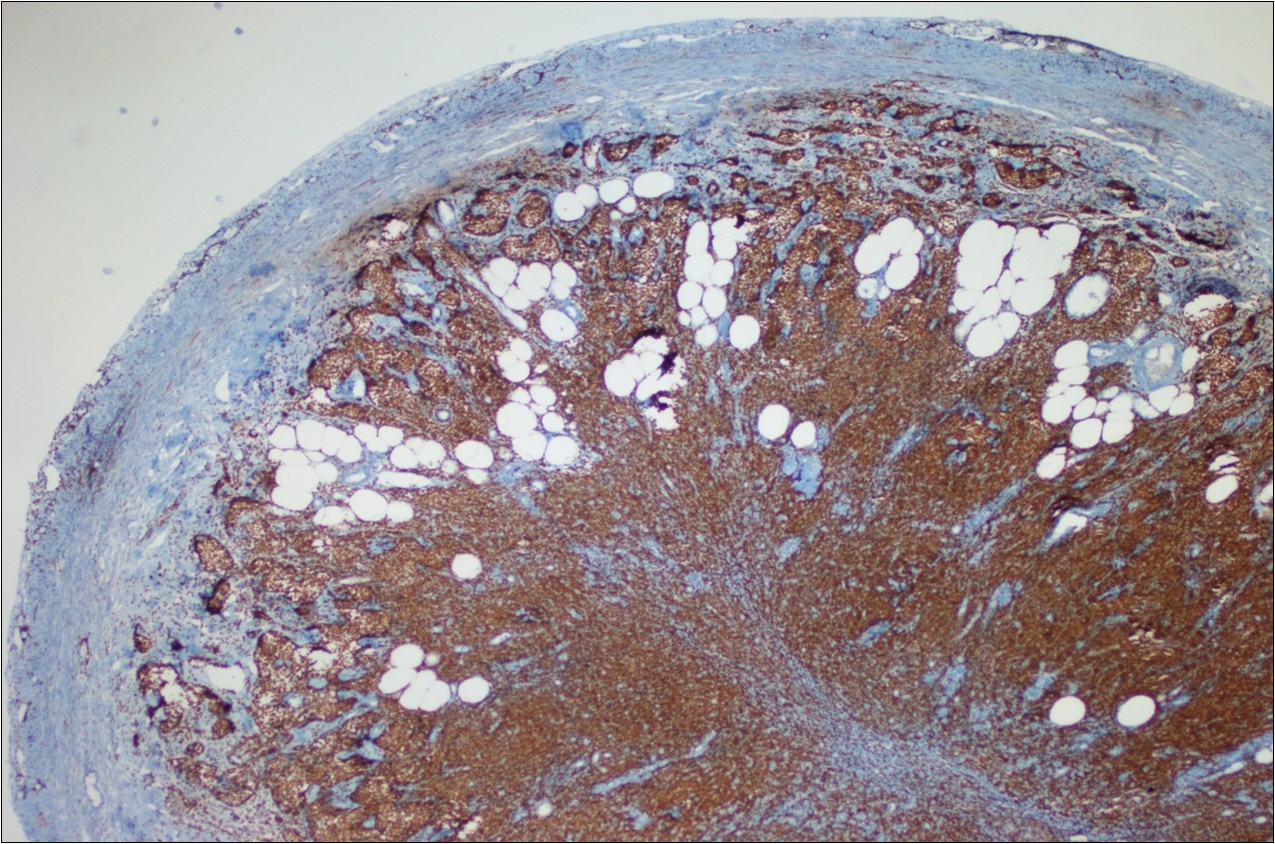

Figure 6.Adenocarcinoma with MALT lymphoma infiltration of lymph node (h&e;200)

Adenocarcinoma with MALT lymphoma infiltration of lymph node (h&e;200)

A 63-year-old woman presented to the Department of General Surgery as an outpatient with abdominal pain. Physical examination showed the signs of acute appendicitis and appendectomy was performed. During microscopic examination, a small focus of atypical monotonous lymphoid cell population was seen and the material was sampled totally. The pathological examination revealed MALT lymphoma (Figure 1), with diffuse positivity of cluster of differentiation (CD) 20 (Figure 2), CD 79a and B-cell lymphoma (Bcl- 2) (Figure 3) with just a few CD3 positive lymphoid cells. However, no evidence of adenocarcinoma was found in the appendectomy specimen. After the diagnosis of lymphoma, a complete colonoscopy was planned and this revealed a solid tumoral mass in the caecum measuring 5x4x4 cm. Computed tomography of the abdomen and pelvis revealed mesenteric lymphadenopathy associated with a mass in the caecum with multiple nodules in liver consistent with metastasis (Figure 4). Frozen sections were not obtained since the treatment method would not be affected. The patient underwent anterior resection with regional lymphadenectomy, with the pathological assessment of the resected specimen revealing a collision tumor consisting of a poorly differentiated adenocarcinoma extending through the muscularis propria with MALT lymphoma (Figure 5). Microscopic evaluation of the 11 regional lymph nodes in the mesentery of the resected colon and liver biopsy showed diffuse infiltration of MALT lymphoma with metastasis of adenocarcinoma (Figure 6). According to immunohistochemistry, atypical lymphocytes were positive for CD 20, Bcl-2, and negative for CD3, CD5, CD10, CD23, Bcl-6, terminal deoxynucleotidyl transferase, and cyclin D1. The proliferation fraction (MIB-1 immunostaining) was approximately 20%. The morphological and immunohistochemical findings were used to confirm the diagnosis of synchronous presentation of MALT lymphoma and colon adenocarcinoma within the caecum, mesenteric lymph nodes and liver metastases.